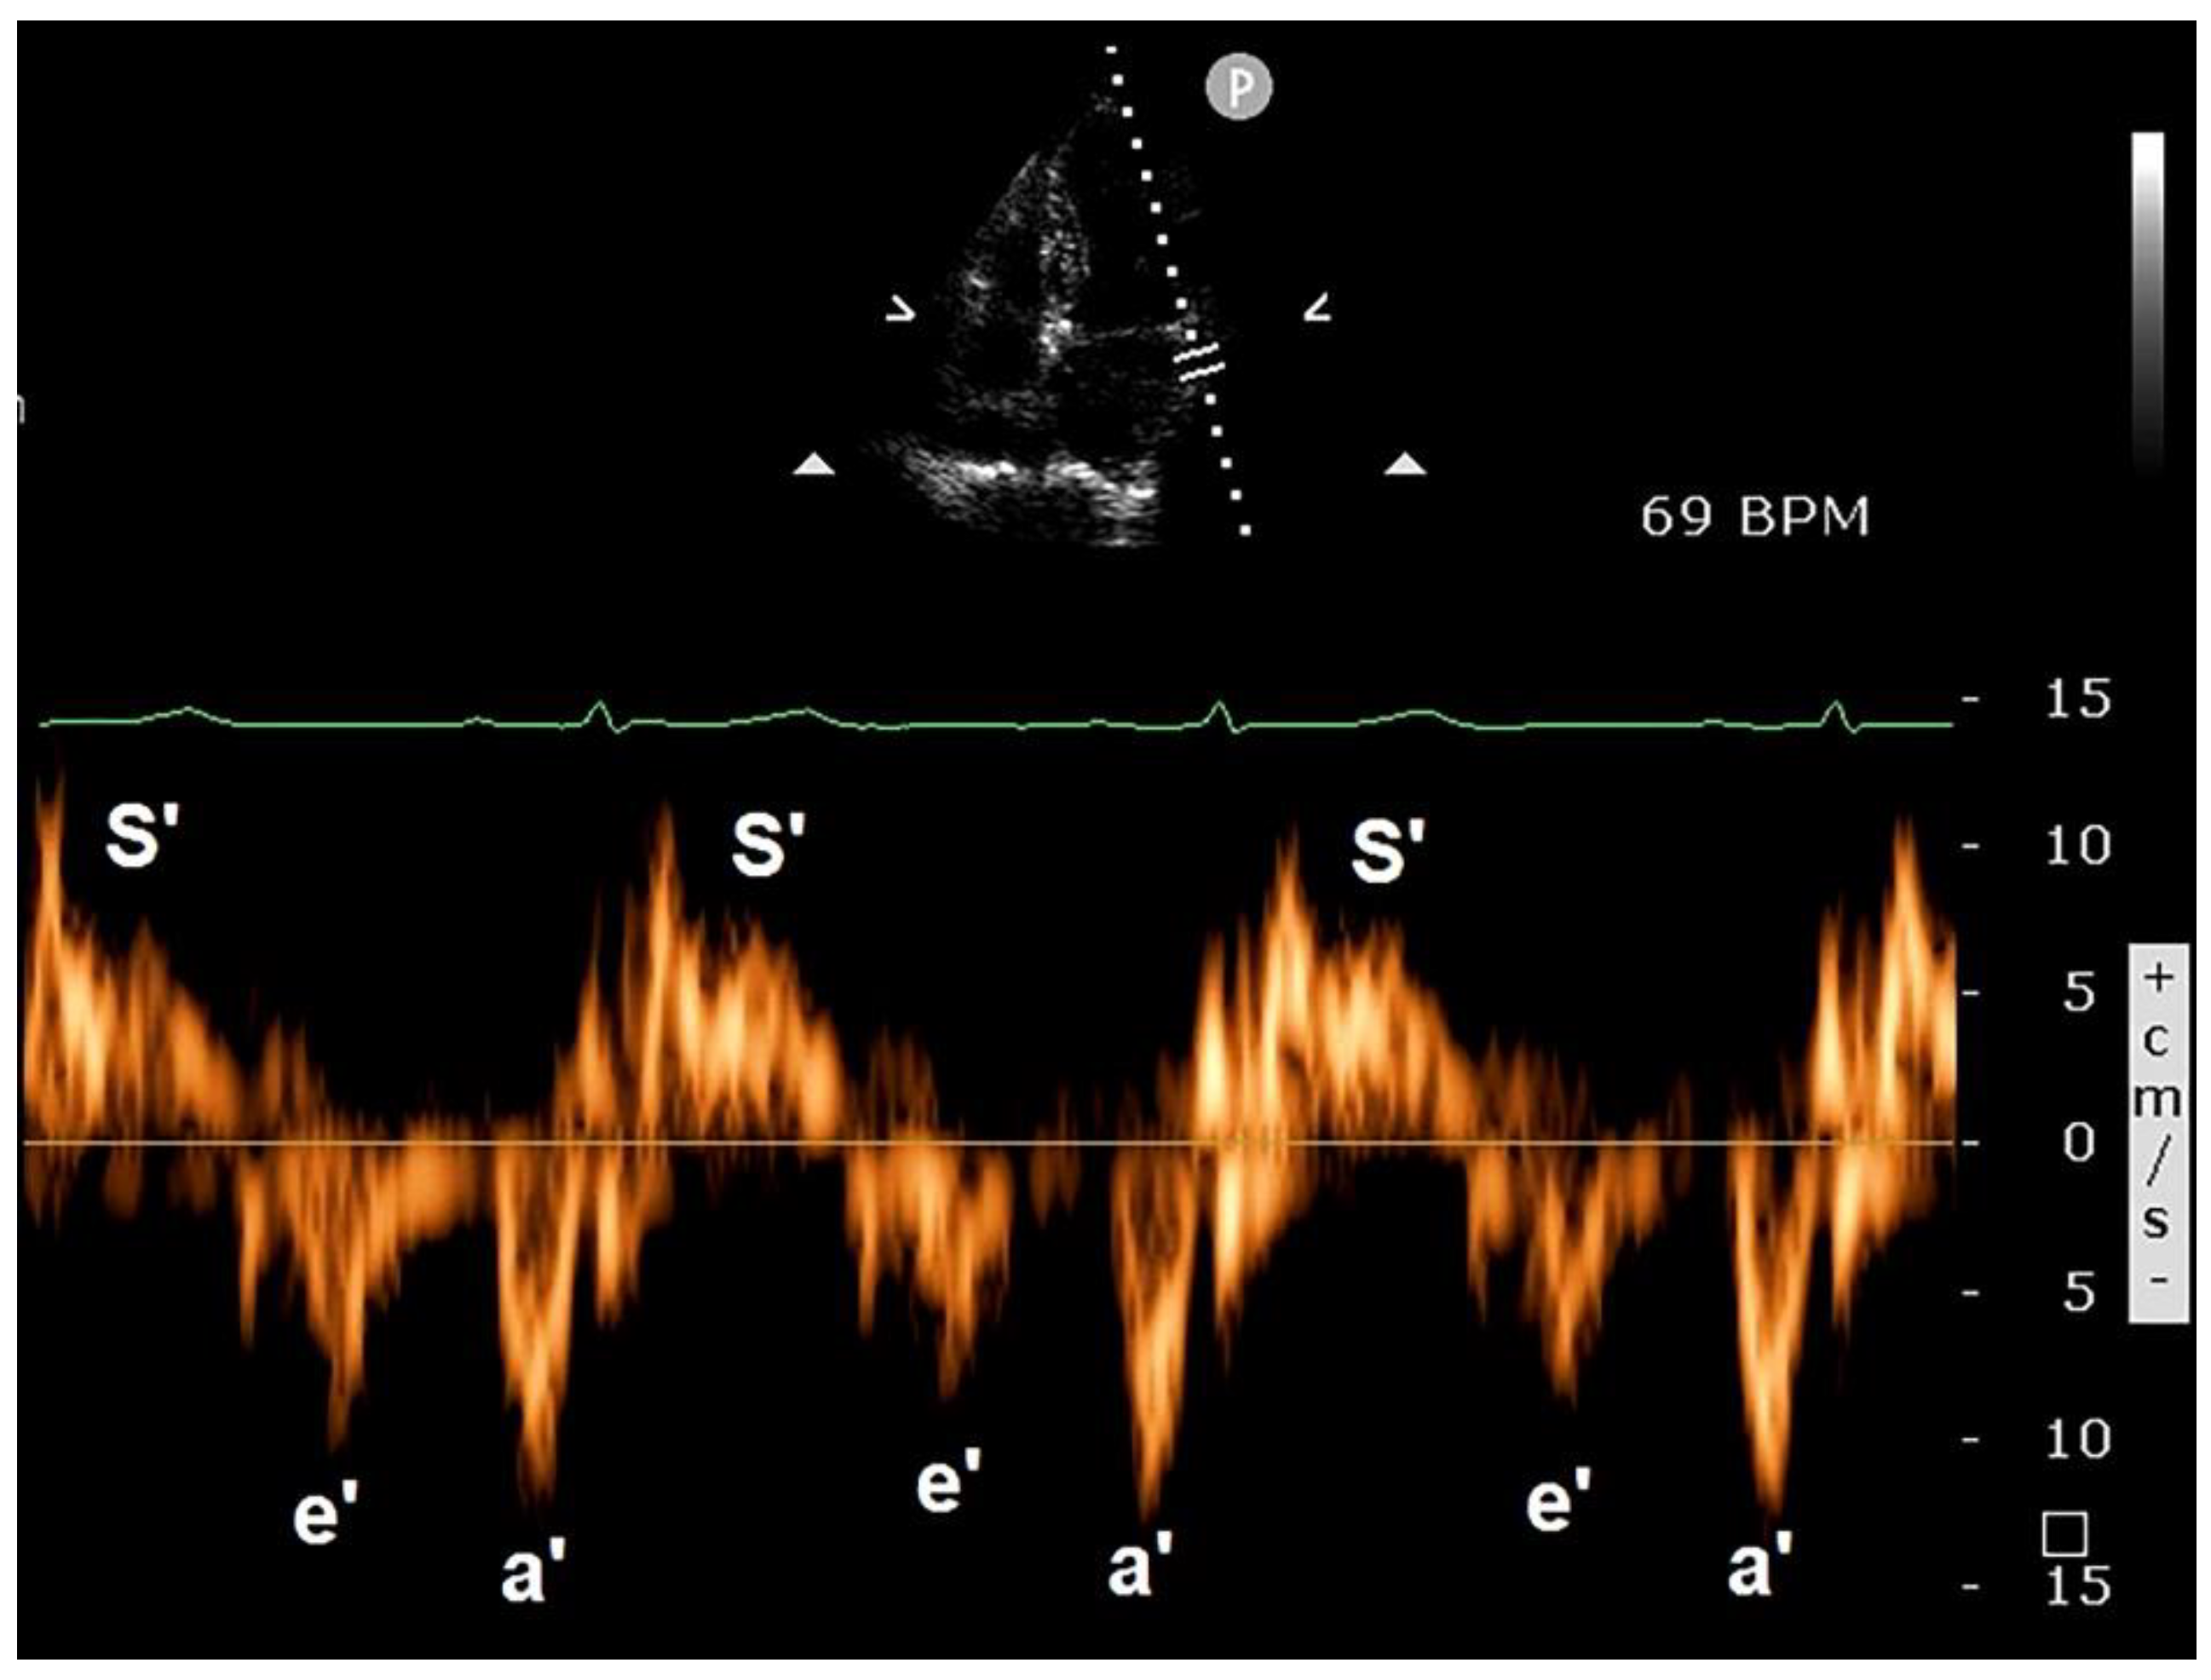

3.3. Clinical Applications of PW-TDI

3.5. Limitations of PW-TDI